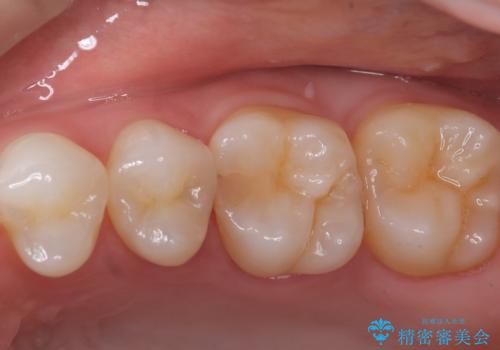

セラミックインレー 虫歯の治療

う蝕を除去し、CRにて裏層をし、セラミックインレーにて修復しました。

ラバーダム防湿をした上で、接着しました。